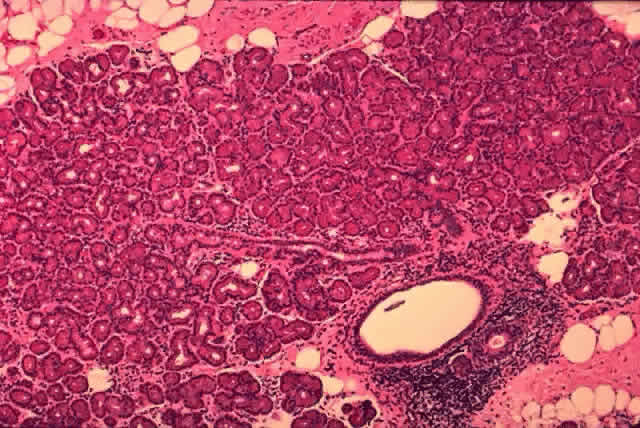

Each lobe of the lacrimal gland is separated into numerous lobules by interlobular fibrovascular connective tissue (Fig. 11). Each lobule, as seen by light microscopy, is composed of two units (Fig. 12): (1) the acinar unit (or secretory unit); and (2) the ductal system. The acinar units are further separated by intralobular fibrovascular connective tissue.

Fig. 11. Lacrimal gland architecture. Each lobe of the lacrimal gland is separated into numerous lobules by interlobular fibrovascular connective tissue. (H & E, original magnification × 5; Courtesy of Ralph Eagle, MD, Philadelphia, PA)

Fig. 12. Lacrimal gland. Each lobule is composed of acinar secretory units (above) and a ductal system. An interlobular duct is seen (lower right). (H & E, original magnification × 25; Courtesy of Ralph Eagle, MD, Philadelphia, PA)

The Acinar Unit (Fig. 13)

Each lobule consists of a complicated grape-like (Fig. 14) arrangement of acini. Each acinar unit (Fig. 15) consists of a central lumen, a continuous inner layer of columnar secretory epithelial cells, and a surrounding interrupted outer layer of irregularly shaped myoepithelial (basket) cells.9